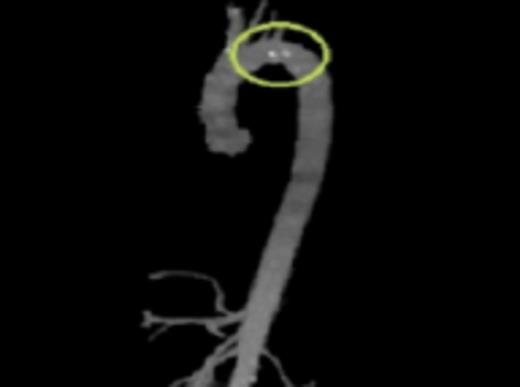

A cross sectional CT-angiogram showing the mobile aortic plaque in the descending thoracic aorta. This image is taken prior to intervention

Initial workup included a transesophageal echocardiogram (TEE) which showed a 0.8cm × 0.9cm highly mobile plaque just distal to the take-off of the left subclavian artery. CT angiography (CTA) was then performed to further delineate the anatomy and to evaluate for the possibility of endovascular stent graft placement. CTA showed a thoracic aortic intraluminal filling defect which represented a small area of clot within an atherosclerotic plaque. The CTA also demonstrated an area of decreased attenuation on the upper anterior portion of the spleen consistent with an older splenic infarct.